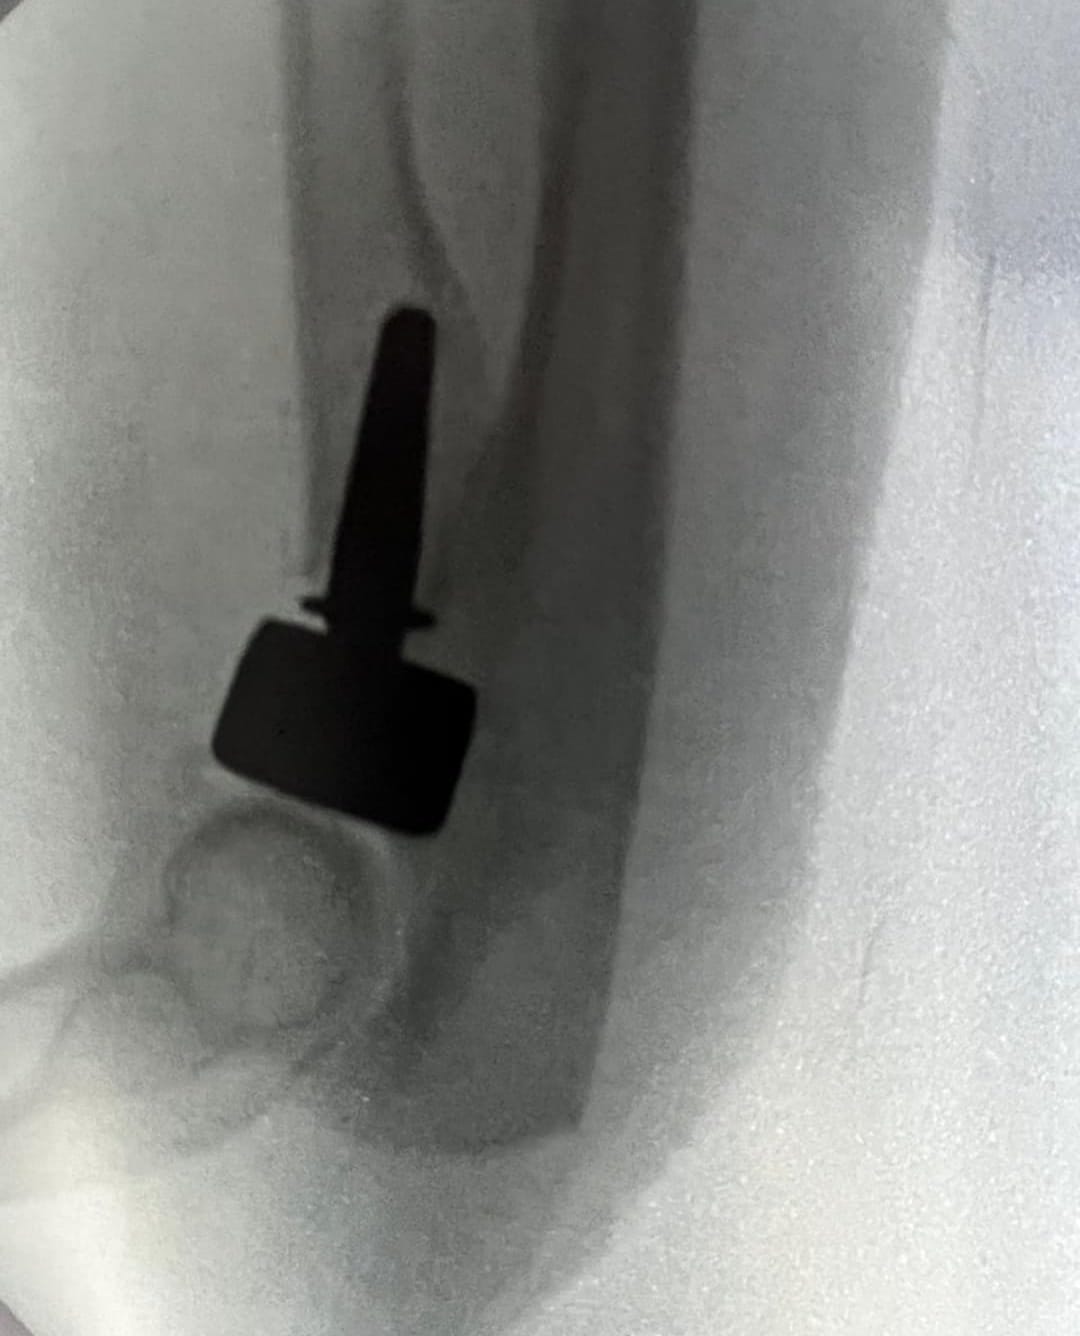

• Cirugía ortopédica reconstructiva

CASOS